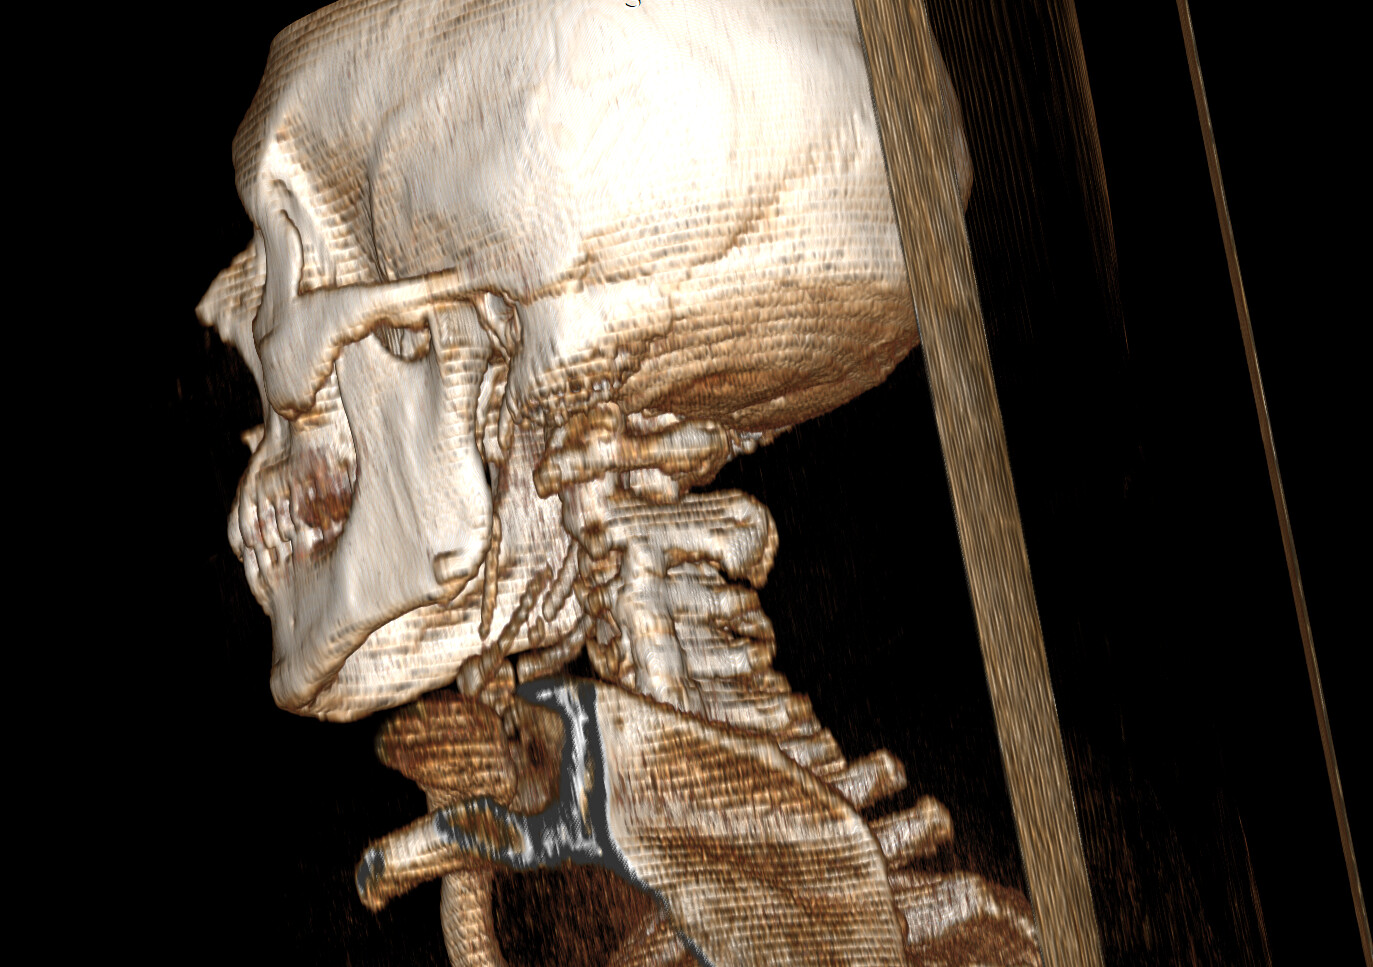

Typically, in the context of vascular ES, the most relevant view is of C1 in the axial view. I’ve attached my own imaging to help you know what to look for. It’s the top vertebrae with a white circle in the top middle:

Wow your right styloid/stylohyoid ligament is almost as long as it can get!! Your left side the styloid is around normal length and then there is a length of normal stylohyoid ligament, followed by a long pocket of calcified stylohyoid ligament.

Crazy styloids! It looks like on the 3D images that there’s a reasonable gap between the styloids & the C1 process, but sometimes it can be more obvious on the axial images, it could be that the digastric muscle is causing compression as @TML saw…